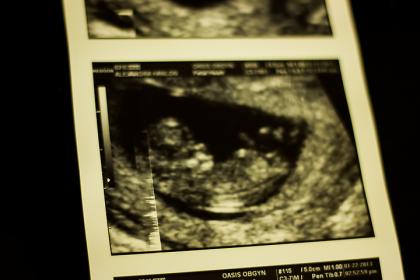

Attachment 8296Attachment 8297

If the second pic is more recent, I would say BOY..how far along r u in these scan pics?

maybe boy.. age of bubs makes a difference

Maybe boy

looks boy on 2nd pic x

I'm hoping for a boy, but I'd be happy either way we have two girls already :)

I'm thinking it could be a :bluecheer: !!!